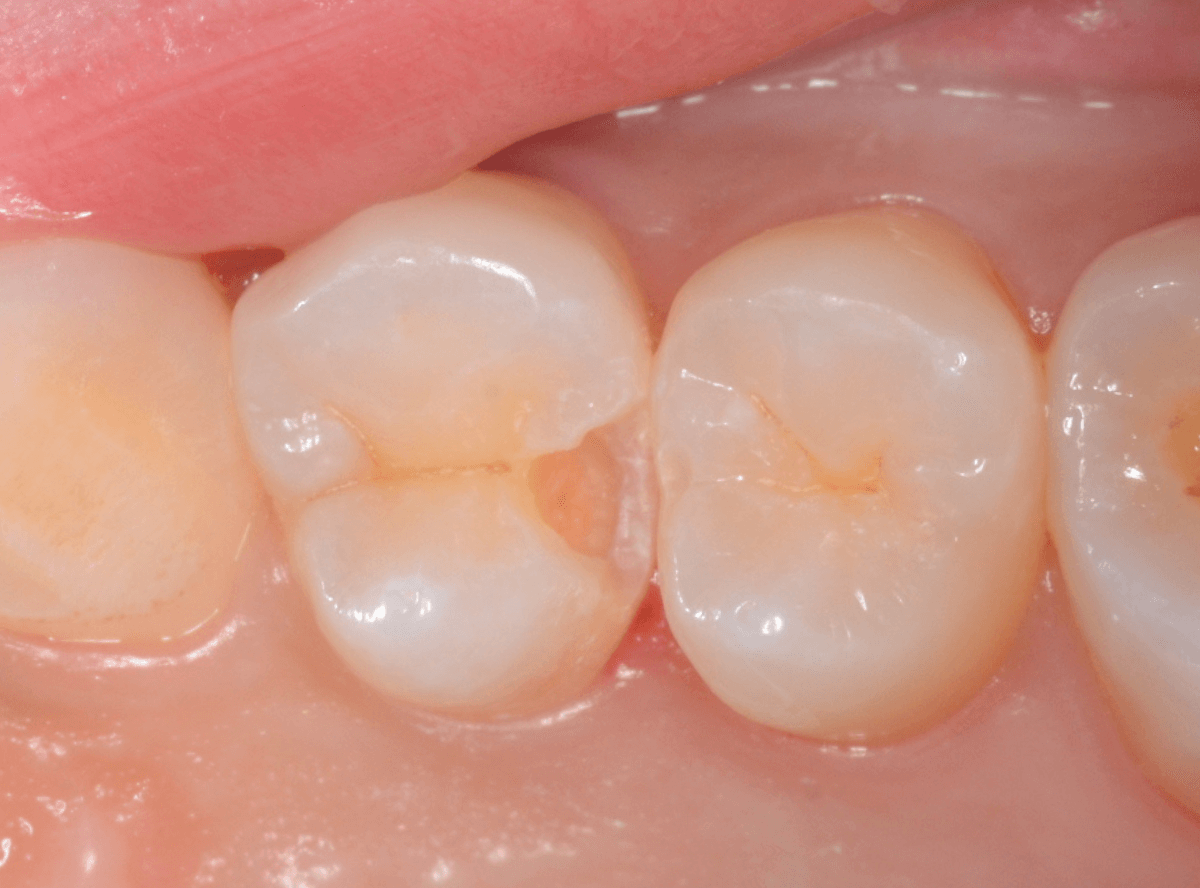

お口の中を拝見すると、数か所アヤシイ箇所がありました。その中の一つです。

この写真では、問題なさそうですね。

角度を変えてみたところです。

ちょっと黒っぽいところが見えますね。